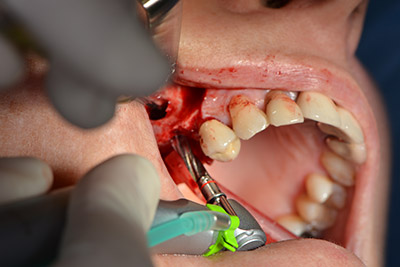

An absorbable membrane was used as the barrier in the buccal direction and covered the augmentation. Finally, saliva-proof sutures were placed (Fig. 15 to 19).

saliva-proof wound closure

Image 19